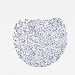

LIVER CANCER - Protein expressioni

A mouse-over function shows sample information and annotation data. Click on an image to view it in a full screen mode. Samples can be filtered based on level of antibody staining by selecting one or several of the following categories: high, medium, low and not detected. The assay and annotation is described here.

Note that samples used for immunohistochemistry by the Human Protein Atlas do not correspond to samples in the TCGA dataset.

Antibody stainingi

Antibody staining in the annotated cell types in the current human tissue is reported as not detected, low, medium, or high, based on conventional immunohistochemistry profiling in selected tissues. This score is based on the combination of the staining intensity and fraction of stained cells.

Each image is clickable and will lead to virtual microscopy that enables deeper exploration of all samples and also displays staining intensity scores, fraction scores and subcellular localization as well as patient and tissue information for each sample.

Antibody HPA000452

Antibody HPA023040

Antibody CAB000134

Carcinoma, Hepatocellular, NOS